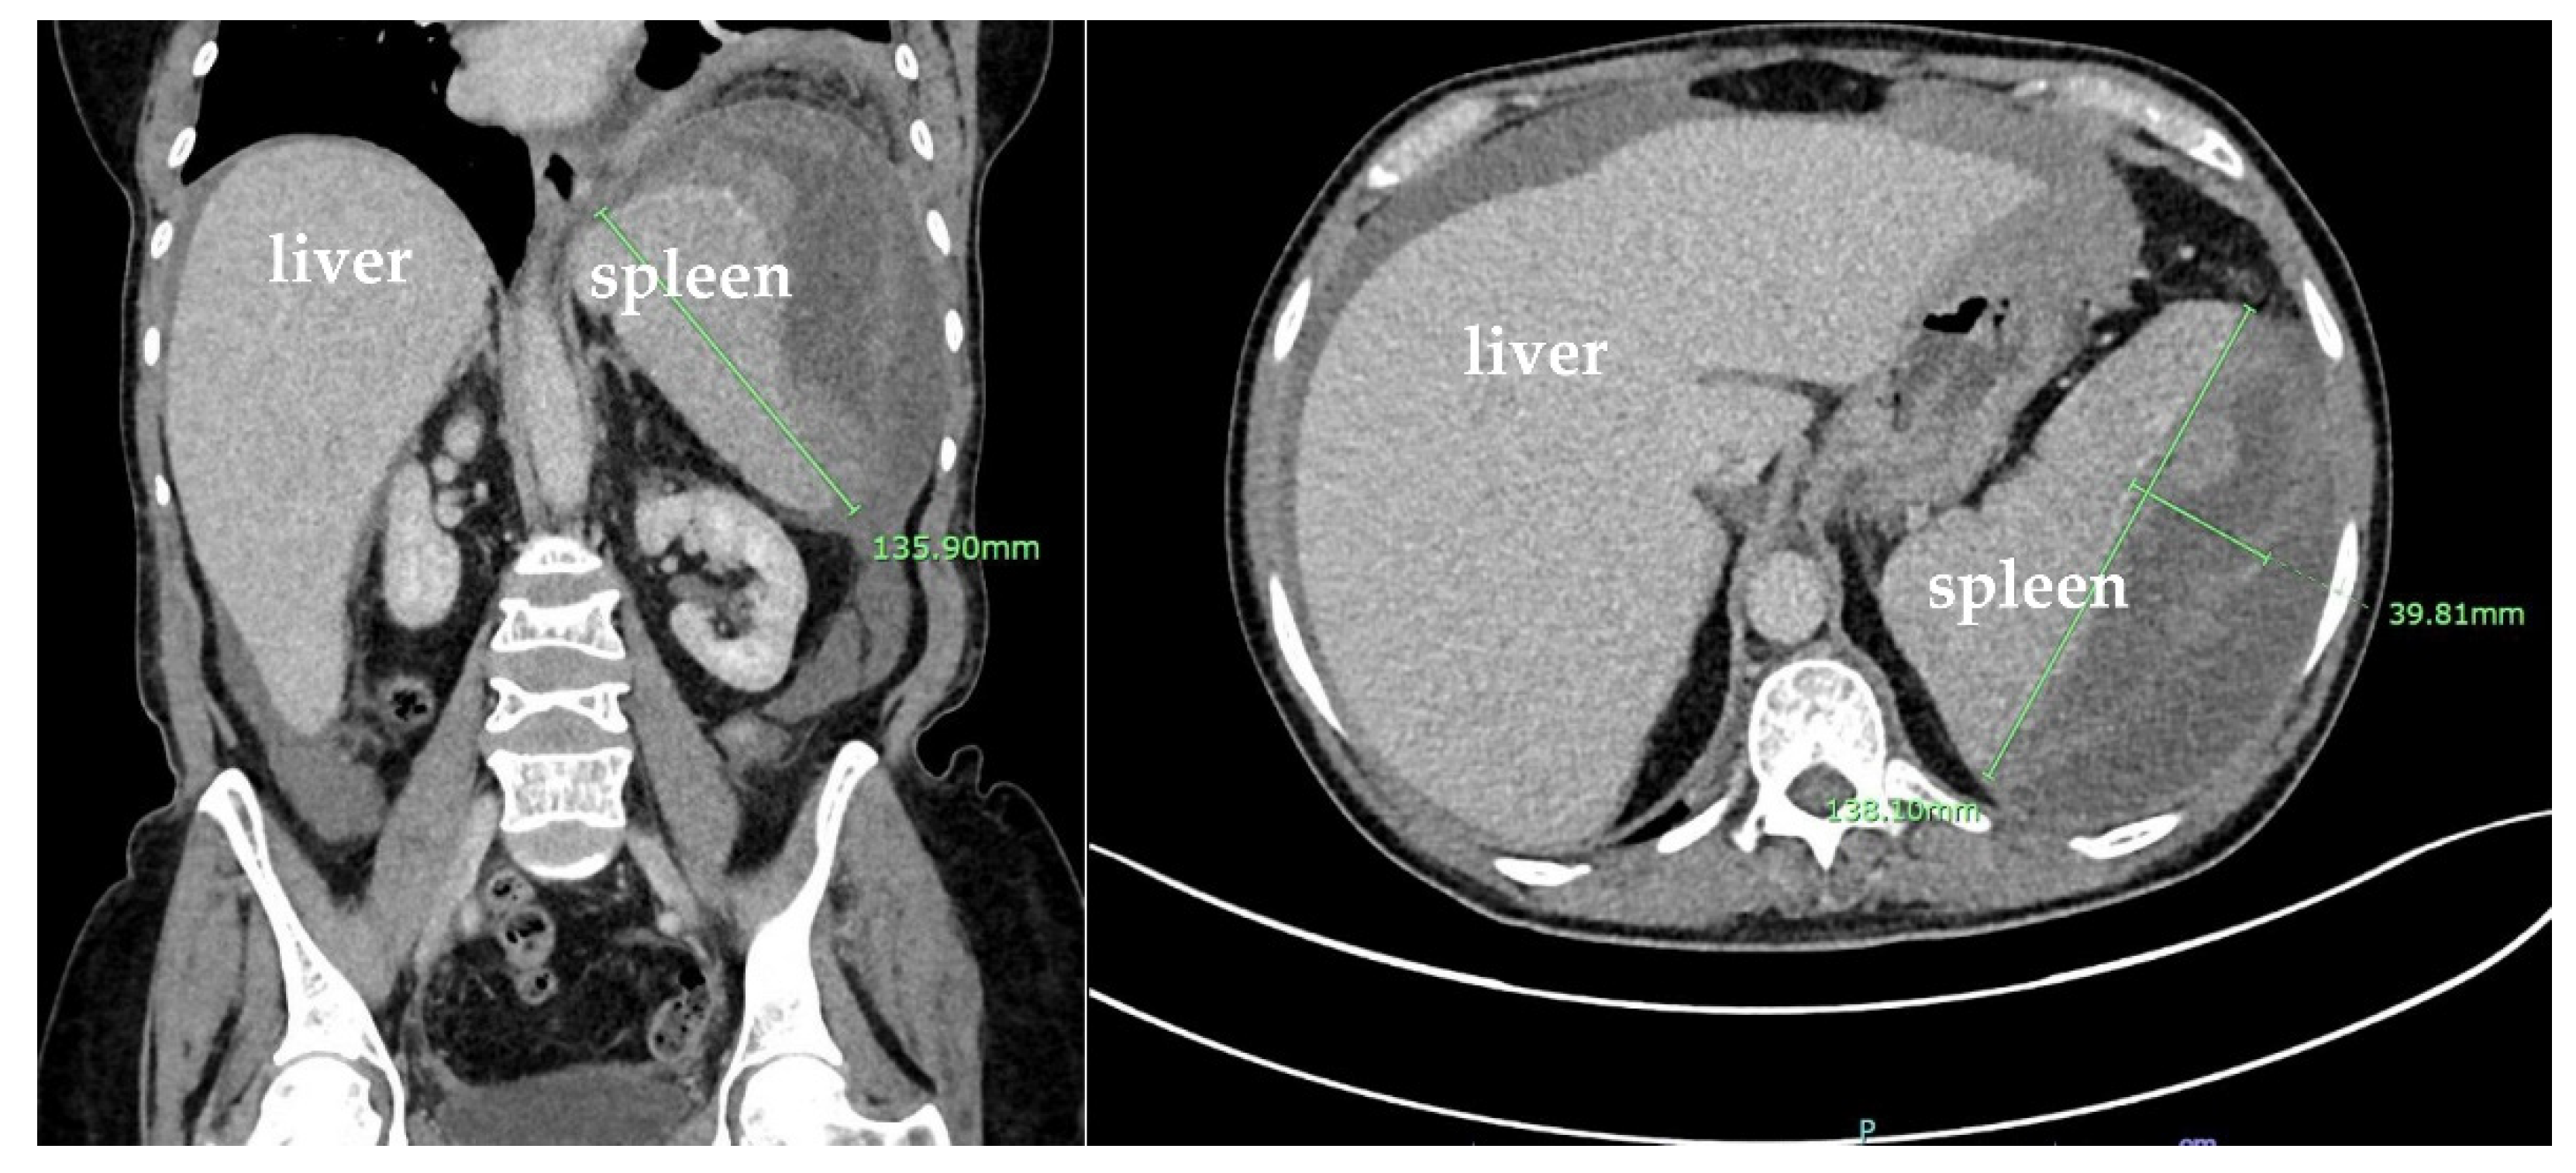

A CTA of the abdomen and pelvis was performed and showed an increase in the size of the splenic subcapsular hematoma, measuring approximately 14.0 × 13.2 × 6.1 cm, and large splenic infarction (Figure 5). Given the new imaging findings and intractable left abdominal pain, the surgery team was consulted. Accordingly, the patient was taken to the operation room for open splenectomy due to splenic rupture and hemorrhage. The spleen was then taken to pathology. On histopathological examination, the spleen was enlarged, weighing 593 g and measuring 16 × 10 × 5.2 cm. The capsule was dark red and had a predominantly posterior laceration, which measured 13.5 cm. Multiple adhesions were also noted (Figure 6A). The cut section revealed a poorly demarcated, dark red, hemorrhagic area located superiorly in the subcapsular area and measuring 10.5 × 7 × 4 cm. Additionally, identified were multiple ill-defined, firm, white-yellow areas comprising approximately 10% of the total cut surface. The remainder of the spleen parenchyma was homogeneous, dark red, and firm (Figure 6B).

Figure 5. Coronal and sagittal plane computed tomography angiogram (CTA) scans with IV contrast of the abdomen and pelvis showing large splenic infarction with an increase in the size of splenic subcapsular hematoma, measuring up to approximately 14.0 × 13.2 × 6.1 cm, with a mass effect on the splenic parenchyma and an increase in the moderate-volume hemoperitoneum.